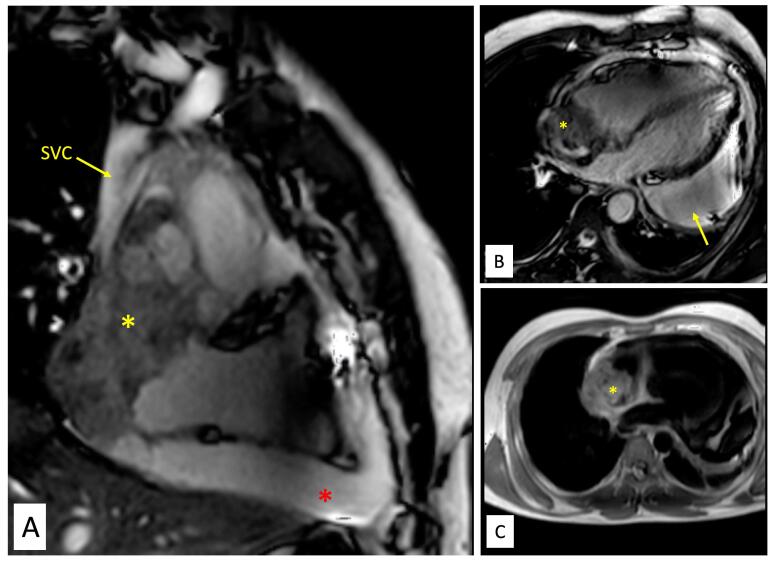

一位28岁男性,有较短的进行性呼吸困难病史,心包大量积液伴心包填塞,超声心动图检查发现右心房有心内肿块。多模态影像显示不规则肿块邻近RA外侧壁,浸润周围心包及上腔静脉。正电子发射断层扫描(PET)证实肿块为代谢活跃病变,并伴有纵隔结构和淋巴结的摄取。经皮心肌膜活检无效后,行开放性手术活检。组织学检查证实为心脏血管肉瘤。不幸的是,患者在活检后出现难治性休克和复发性大量心包积液(出血性)而死亡。该病例强调了结核流行地区心包积液的诊断困境,多模态成像在确认心脏恶性肿瘤中的作用以及此类患者的不良预后。

A 28-year-old male with a relatively short history of progressive dyspnea and a large pericardial effusion with tamponade was found to have an intracardiac mass localized in right atrium (RA) on echocardiography. Multimodality imaging revealed an irregular mass abutting the lateral wall of RA, with infiltration into surrounding pericardium and superior venacava. Positron emission tomography (PET) scan confirmed the mass as metabolically active lesion, along with uptake in mediastinal structures and lymph nodes. After an unrewarding percutaneous endomyocardial biopsy, open surgical biopsy was performed. Histologic examination confirmed the diagnosis of cardiac angiosarcoma. Unfortunately, patient had refractory shock and recurrent massive pericardial effusion (hemorrhagic) after biopsy and succumbed. The case highlights diagnostic dilemma of pericardial effusion in tuberculosis-endemic areas, role of multi-modality imaging in confirming cardiac malignancy and poor outcome of such patients.